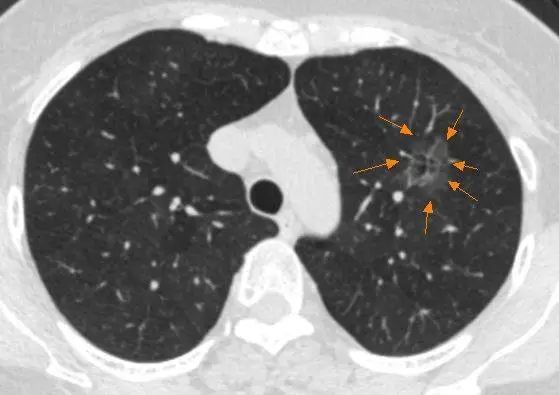

胸部CT是肺癌术后最常用的临床影像学复查手段,必要时可采用胸部增强CT。